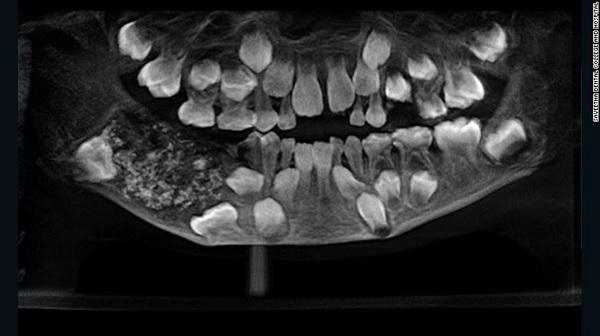

| Subject | [약혐]치과에서 보면 소름 돋을 엑스레이 사진 |

둘 다 엄청 힘든 케이스인가봐요.... 윗 사진은 어금니가 엄청 많이 있는 케이스, 아래 사진은 작은 치아종양(?)같은게 어금니 대신 그 자리를 메우고 있는 ㅠㅠ 다 제거하고 임플란트 해야하나봐요 0